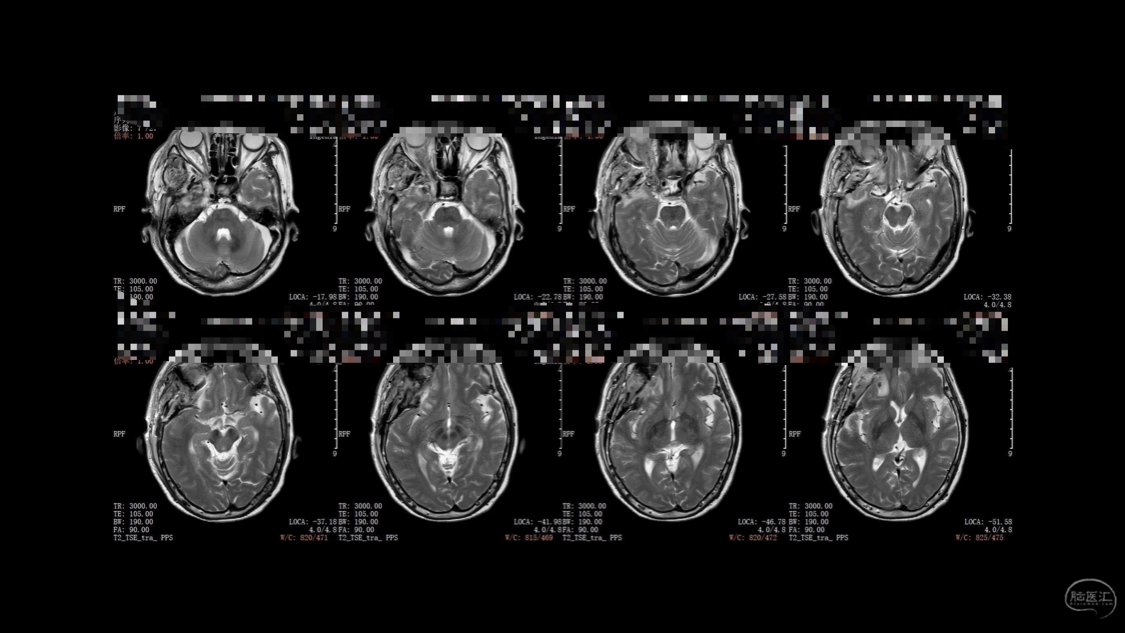

陈保东教授手术作品-右眶内及海绵窦旁孤立性纤维瘤